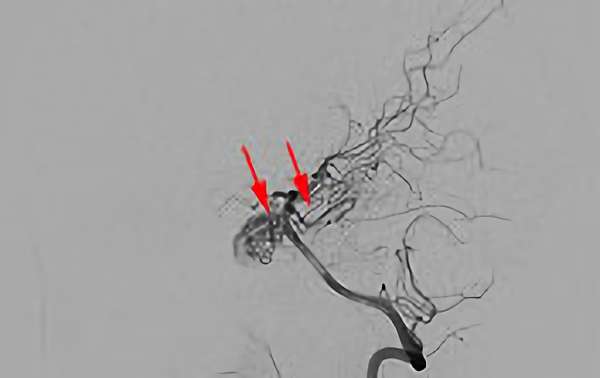

No.1620 手術前

No.1620 手術中

No.1620 手術後